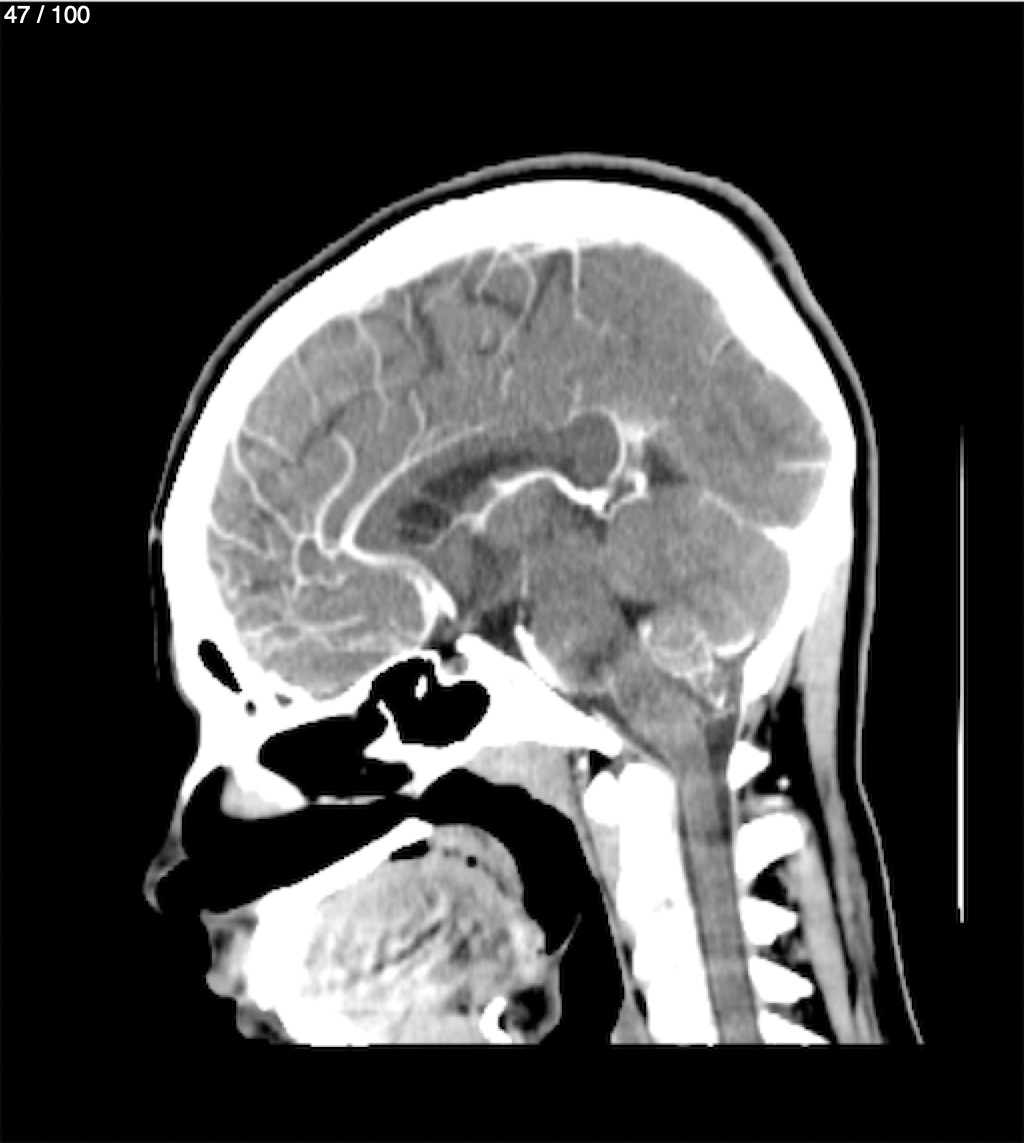

Fernando Daniel Gutierrez Caraba - Tc. Craneo Syc